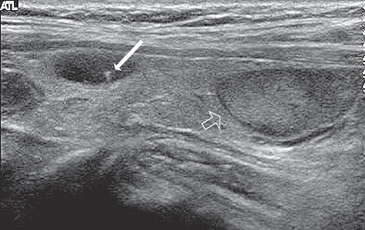

Figura 1. Microcarcinoma de 8 mm.

Los nódulos tiroideos se hacen palpables cuando alcanzan aproximadamente 10 mm de tamaño, dependiendo de su localización. Cuando la palpación era la principal manera de identificar nódulos, este diámetro era el límite para realizar una biopsia. Aunque las normas de la Asociación Americana de Endocrinólogos Clínicos (AACE) y la Asociación Americana de Tiroides (ATA) continúan usando 10 a 15 mm como el umbral práctico9,10 para seleccionar nódulos que necesitan de una PAAF, se ha demostrado que el tamaño no es un buen indicador para predecir malignidad. Son varios los trabajos que muestran que la prevalencia de cáncer es similar en nódulos mayores o menores de 10 mm11. La Sociedad de Radiólogos en Ultrasonido recientemente llegó al consenso de que, más que fijar un umbral de tamaño, debe usarse el aspecto ecográfico del nódulo como criterio de selección, tanto en el nódulo solitario como en la glándula multinodular4. En nódulos mayores de 10 mm no habría una diferencia significativa en el porcentaje de malignidad, aunque hay una tendencia que indicaría que la tasa de malignidad es más alta en nódulos mayores de 30-40 mm. El cáncer papilar menor de 10 mm se ha definido como microcarcinoma (Figura 1) y su frecuencia ha aumentado gradualmente en los últimos años12. Persiste el debate si este aumento es real o simplemente se debe al uso masivo de la ecografía cervical y la PAAF guiada por ecografía, lo que permite identificarlos precozmente. La presencia de múltiples nódulos no disminuye la probabilidad de cáncer tiroideo por paciente y el nódulo dominante por mayor tamaño no es necesariamente el que contiene el cáncer, ya que en aproximadamente un 30% el cáncer está en el nódulo no dominante4. Independiente del tamaño los nódulos casi completamente quísticos, sin otras características sospechosas, probablemente no requieren de biopsia.